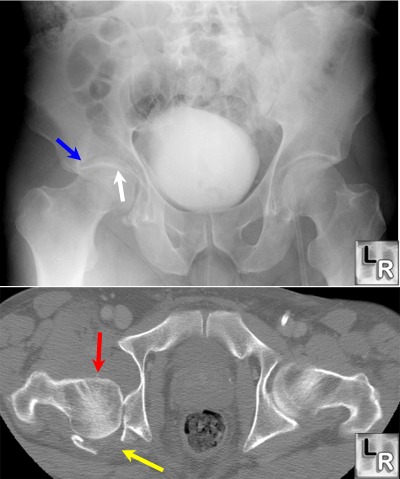

Left hip two weeks after an in-car crash. He could only accident. On examination, his left hip was slightly flexed and had minimal internal rotation. Wiss DA, Cozen L. Posterior fracture disloca-tion of the hip with fractures of the femoral head. Clin Orthop Relat Res 1985; ... Fetch Full Source

Car accident when the knee strikes the dash and the force is transmitted up the bone. to distinguish from the shaft fracture, like a . hip fracture. Fractures of the knee cap are quite commonly associated, as are fractures and dislocations of the hip socket. ... Fetch Here

Bilateral Traumatic Hip Dislocation